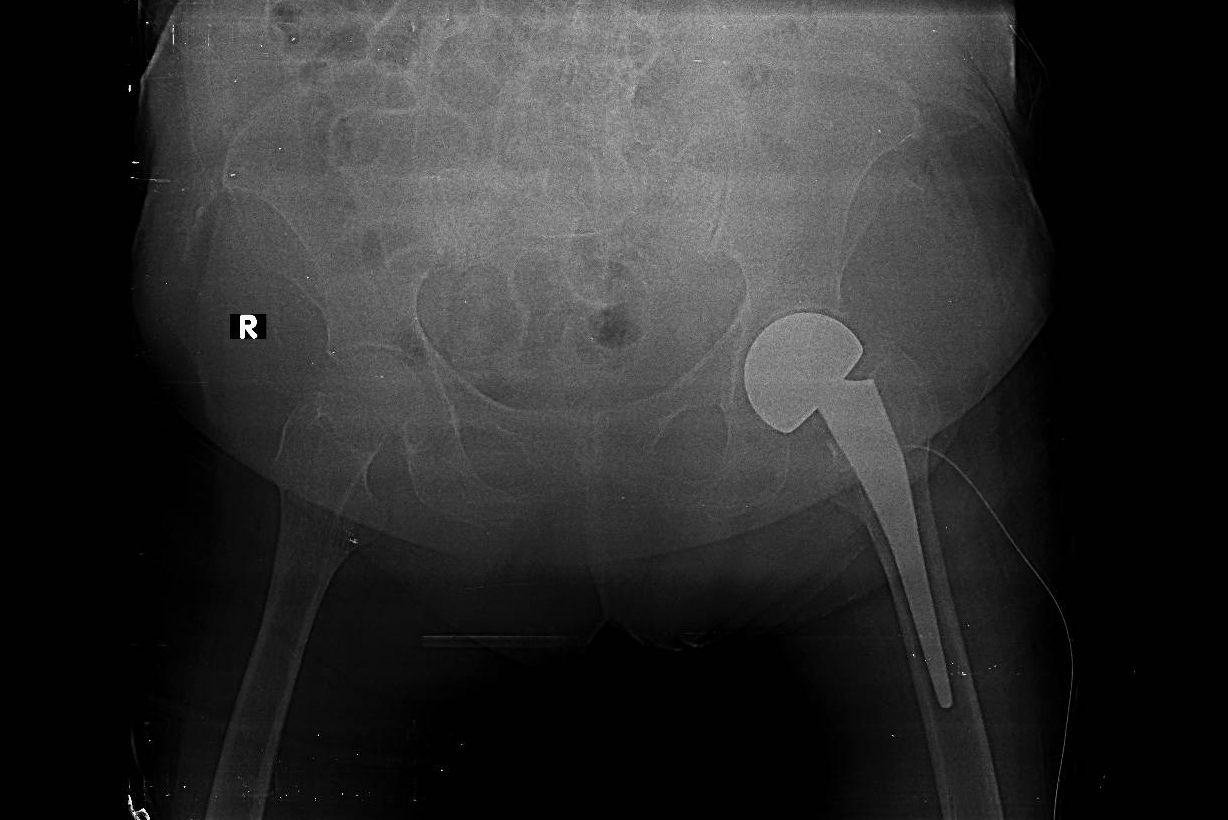

1.png

Hình X-quang khớp háng của người bệnh sau phẫu thuật

Đầu tháng 8/2020, các bác sĩ tiến hành thay khớp háng bán phần cho người bệnh, phối hợp việc gây tê tủy sống và gây tê ngoài màng cứng liên tục. Ca mổ diễn ra thuận lợi. Ngay ngày đầu tiên sau mổ, người bệnh đã có thể tự ngồi dậy xoay trở. 2 tuần sau phẫu thuật đầu tiên, người bệnh đang được tập vật lý trị liệu, chuẩn bị cho phẫu thuật thay khớp gối thì đột ngột xuất hiện triệu chứng đau dưới sườn phải, sốt cao, vàng da. Sau khi xét nghiệm, siêu âm và chụp CT bụng, các bác sĩ phát hiện người bệnh bị sỏi đường mật biến chứng. Nếu không can thiệp kịp thời, người bệnh có nguy cơ nhiễm khuẩn nặng, có thể tử vong.